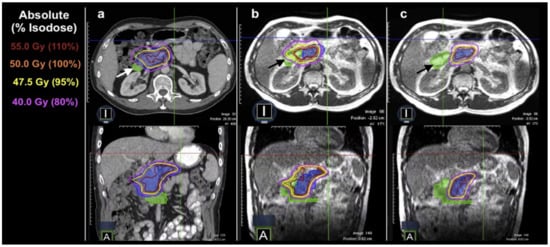

- Henke, L.; Kashani, R.; Yang, D.; Zhao, T.; Green, O.; Olsen, L.; Rodriguez, V.; Wooten, H.O.; Li, H.H.; Hu, Y.; et al. Simulated Online Adaptive Magnetic Resonance–Guided Stereotactic Body Radiation Therapy for the Treatment of Oligometastatic Disease of the Abdomen and Central Thorax: Characterization of Potential Advantages. Int. J. Radiat. Oncol. Biol. Phys. 2016, 96, 1078–1086. [Google Scholar] [CrossRef]

- Bohoudi, O.; Bruynzeel, A.; Senan, S.; Cuijpers, J.; Slotman, B.; Lagerwaard, F.; Palacios, M. Fast and robust online adaptive planning in stereotactic MR-guided adaptive radiation therapy (SMART) for pancreatic cancer. Radiother. Oncol. 2017, 125, 439–444. [Google Scholar] [CrossRef]